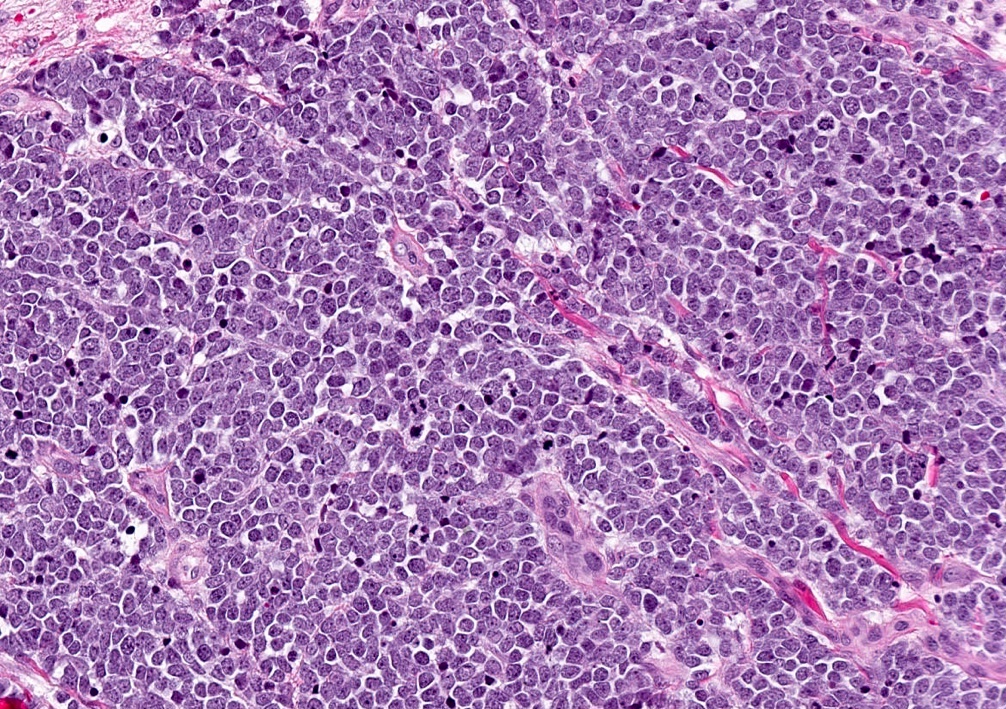

Microscopic (histologic) description

- Expansile, nodular or diffusely infiltrative tumor within the dermis, variably in subcutis

- Variable mixture of nodules, sheets, nests and trabeculae of neoplastic cells

- Generally, small round blue cell tumor with high N:C ratio, round / oval nuclei, finely dispersed chromatin (salt and pepper), indistinct nucleoli and scant cytoplasm

- Conspicuous mitoses and apoptotic bodies

- Variable nuclear molding and crush artifact

- Majority of cases display pure neuroendocrine morphology (pure Merkel cell carcinoma)